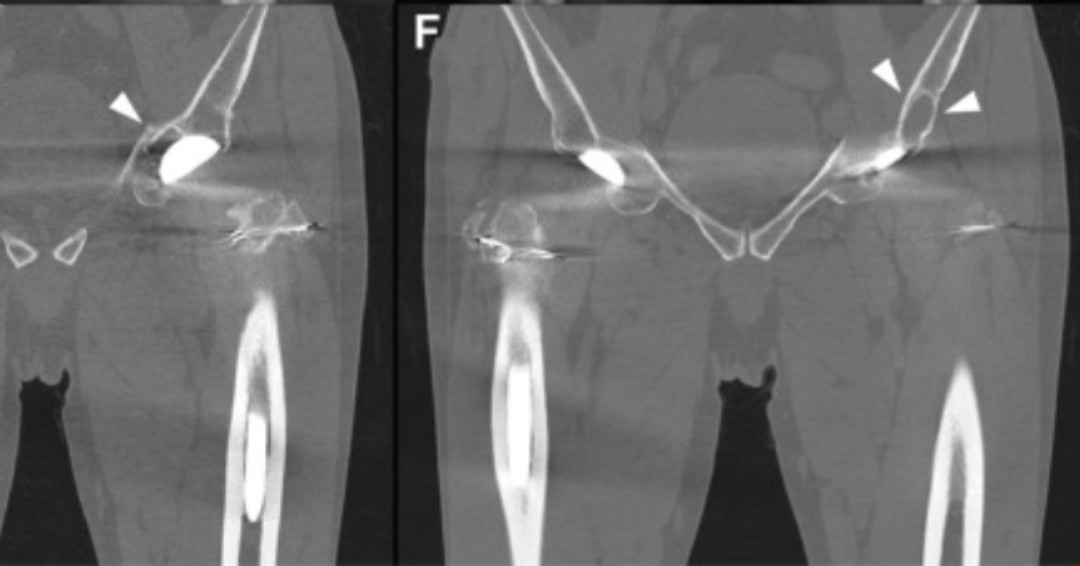

Routine CT for patients who underwent THA with CoC bearings > 20yr ago revealed osteolysis and suspected chip fractures of the ceramic liner. CT in this cohort should be selectively performed for patients who have relevant clinical symptoms. https://t.co/1atyssbLbY